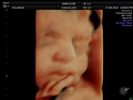

Fotografías de ecografías 4D HD/5D

Haga click sobre las imágenes para ampliar